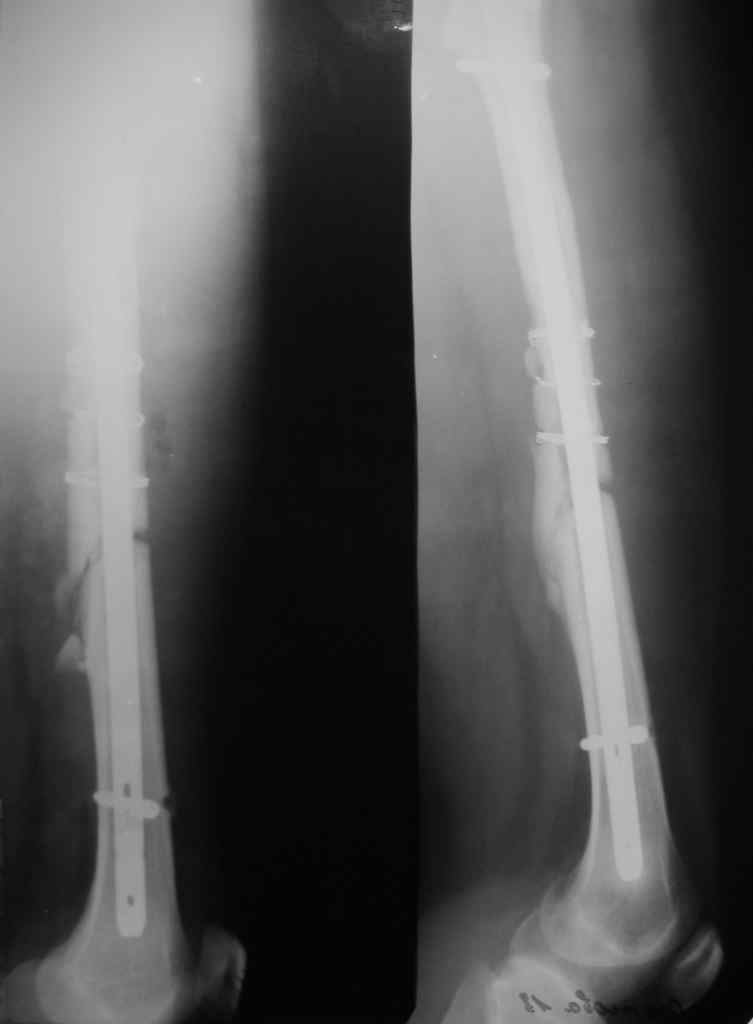

Перелом стержня, серкляж

Поступила молодая,маленькая девочка 18 лет с болями в левом бедре. Из истории:автодорожная травма в ноябре 2005 года, тогда же оперировалась данным способом. Проживает в селе и как правило в таких случаях выпала из поля зрения ведущего доктора.

Ноябрь 2005г. и 18 лет это не 6-8мес это год. на последних снимках разве мы видим элементы "ЗДОРОВОЙ" консолидации сдесь должна быть серьезная гипертрофическая мазоль.

на мой взгляд, выбирать конечно Вам. необходимо удалить стержень, убрать серкляжи под которыми Вы увидите "проблемную" кость. обязательно произвести костную аутопластику "вязанкой хвороста" дать компрессию предварительно заблокировав дистально в двух плоскостях и хорошую остеотропную терапию, раннюю нагрузку. и обследуйте больную на маркеры регенерации. Стержень длинноват и винты бы покороче. С Уважением Куликов.